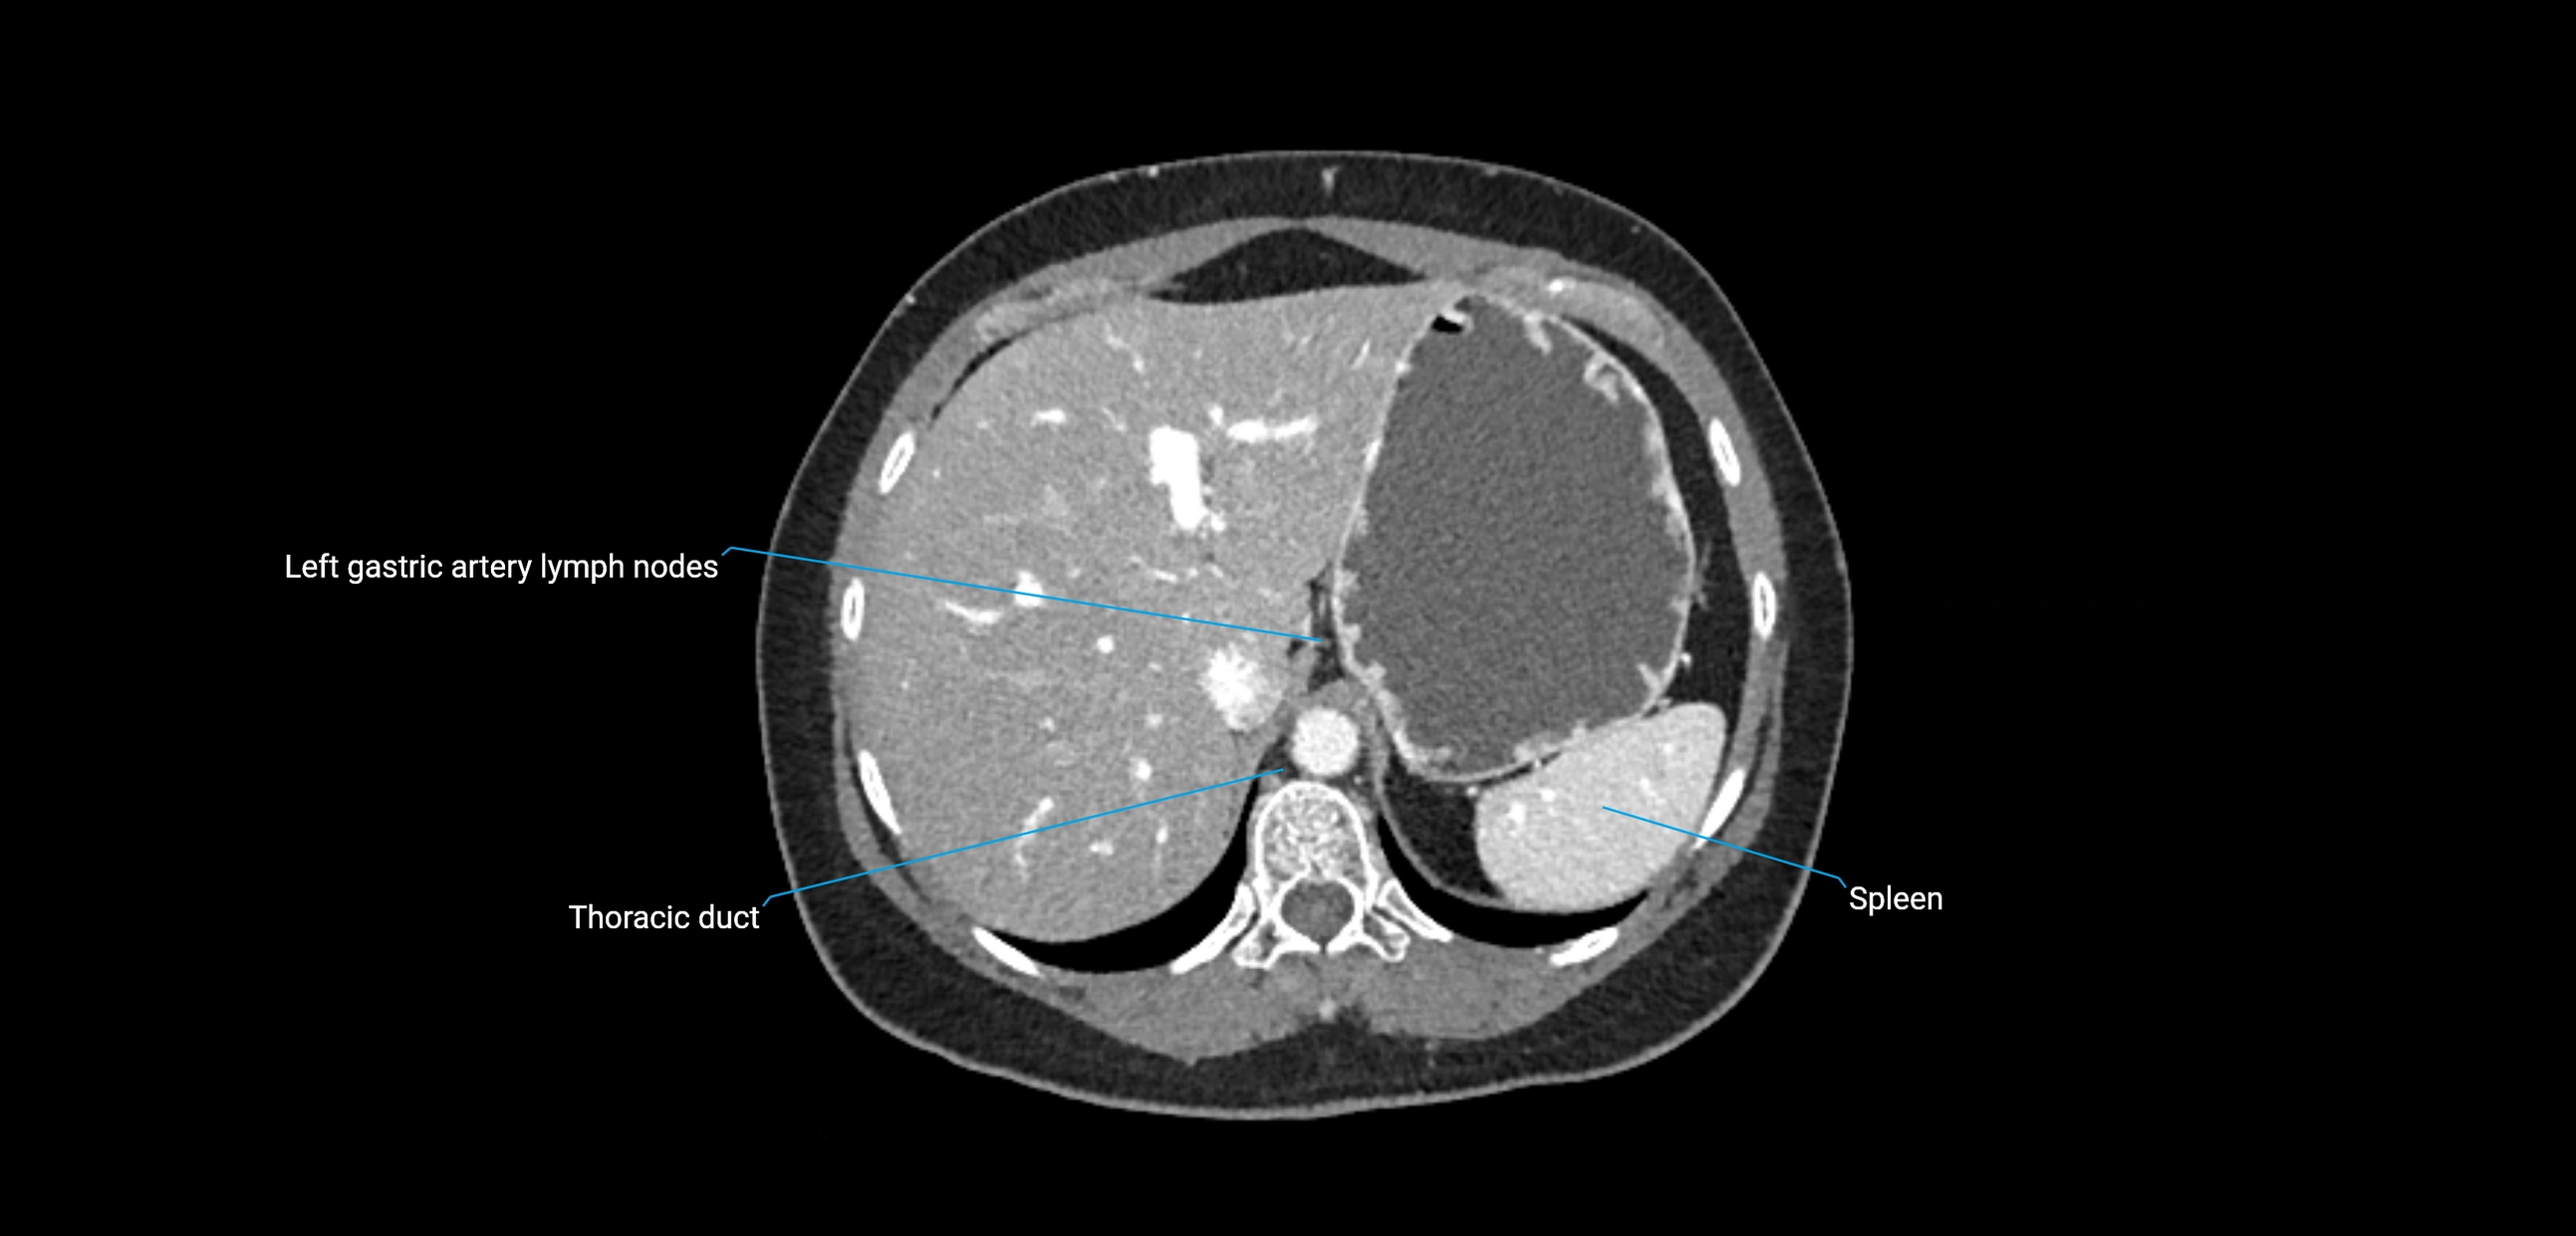

CT Appearance

CT Post-Contrast:

• Normal nodes enhance homogeneously

• Malignant nodes may show heterogeneous enhancement, central necrosis, or conglomerate formation

• Size >1 cm short axis is suspicious, though morphology and distribution are equally important

CT Venography (CTV):

• Demonstrates nodal encasement or compression of adjacent vessels (aorta, IVC, renal veins)

• Useful in staging testicular and ovarian malignancies